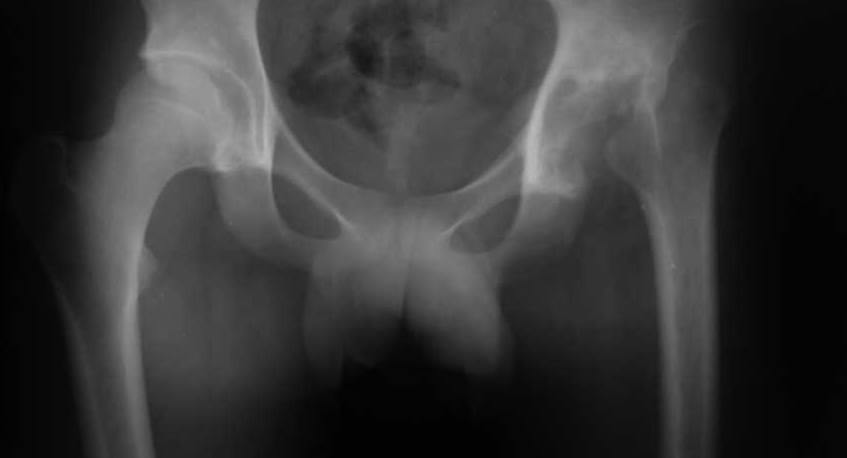

Ув. коллеги. пациент 19 лет, 4 мес назад перене гнойный коксит с затеками и т.д, 3 мес назад -

резекция головки, санирование очага. В настоящее время, кровь спокойная, СРБ - отр, рана

зажила первично. Свищей нет и не было, т-ра в N. В какие сроки, по вашему мнению, целесообразно

выполнить эндопротезирование, какие критерии?

Имя     : таз.jpg